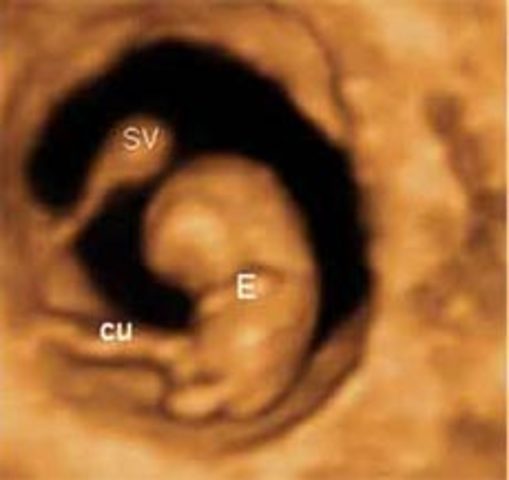

Semana 5

Comienzo del "período embrionario"; es decir, cuando se desarrollan todos los principales sistemas y estructuras del bebé.

Las células del embrión se multiplican y comienzan a asumir funciones específicas. Se desarrollan todas las células sanguíneas, las nefronas y las neuronas. Los rasgos externos del bebé empiezan a formarse.

El cerebro, la médula espinal y el corazón del bebé empiezan a desarrollarse. El tracto gastrointestinal del bebé comienza a formarse.